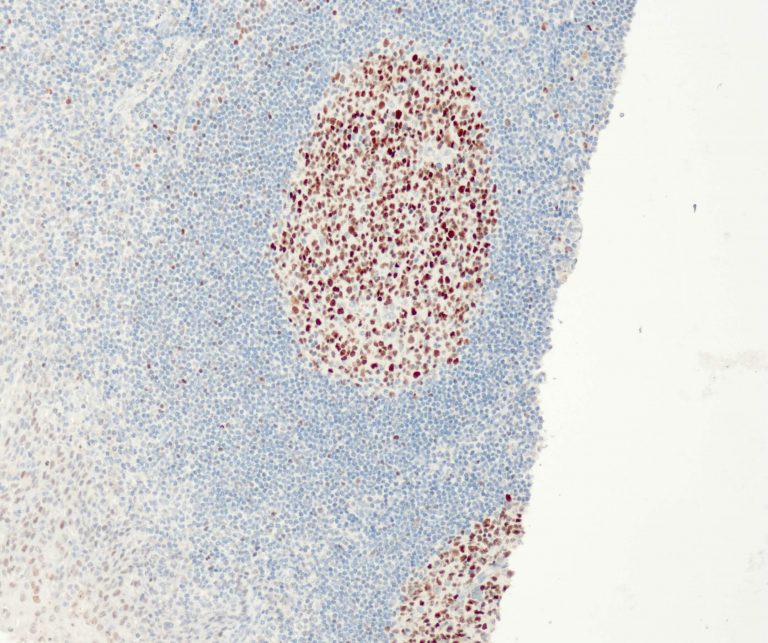

Vascular Pathology

Gastrointestinal (GI) Pathology

General Marker

Breast Pathology

Endocrine Pathology

Gynecological Pathology

Neuropathology

Infection Markers

Lung Pathology

Urinary Tract Pathology

Transplantation Pathology

Soft Tissue Pathology

Hematopathology